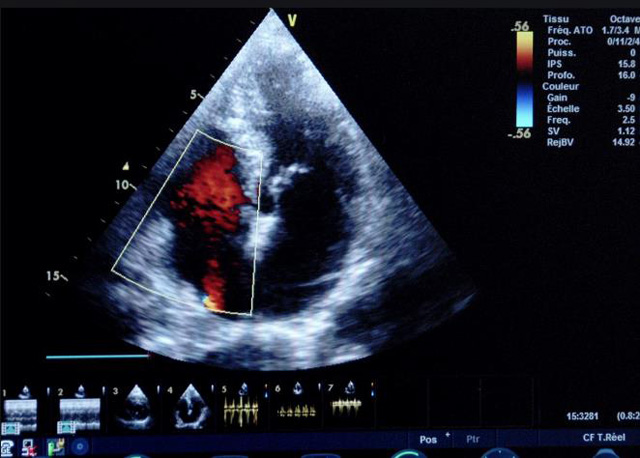

二、彩色室壁運動分析

(一)基本原理彩色室璧運動分析,從整體散射數(shù)據(jù)中識別心內(nèi)膜邊界,并與前一幀彩色不同,心臟收縮或舒張期開始到結(jié)束時心內(nèi)膜的全部過程。每一次順序顯示結(jié)束后,原來的彩色自動消失,以便進入下一個顯示過程。其結(jié)果是獲得對應(yīng)于每一個心動周期的彩色顯示,描繪特定周期內(nèi)室壁運動的時間運動軌跡。

(二)操作步驟根據(jù)背向散射數(shù)據(jù)中將心內(nèi)膜運動的位移過程分類為組織或血液的原理,邊緣檢測跟蹤心內(nèi)膜和血液的界面。橙色表示收縮期的開始,收縮期不同時相逐幀顯示色彩均疊加在收縮末期最后一幀圖像中。檢查時,可按以下步驟進行:

①顯示較為理想的二維圖像,常用切面有心尖四腔心、二腔心、左心室長軸和左心室乳頭肌水平短軸切面。

③啟動CK系統(tǒng),啟動后劃定感興趣區(qū)域。同時記錄的心動圖R波頂點為舒張末期,T波終點為收縮末期,顯示RT間期的CK彩階圖,連續(xù)記錄3~ 5個心動周期。

(三)檢測節(jié)段性室壁運動異常,研究冠心病患者左心室功能和分析局部室壁運動過程中。測量每一節(jié)段室壁的運動量,運動正常的節(jié)段彩帶色彩均勻?qū)哟喂庹?。運動減弱的節(jié)段,厚度薄層次不全。心內(nèi)膜位移幅度和速度均減低。心內(nèi)膜位移幅度和速度甚低或難以測得。正常的多層彩帶消失,呈現(xiàn)紅色色帶,心內(nèi)膜位移呈負向,幅度和速度亦減低。急性心肌梗死的患者中可用于識別存活心肌抑或壞死心肌。多巴酚丁胺負荷試驗存活心肌的心內(nèi)膜位移幅度增高,停藥后即消失,而壞死心肌則無上述表現(xiàn)。實時檢查冠心病的節(jié)段性室壁運動異常,有時候通過發(fā)現(xiàn)局部心肌運動的時相異常,對于心臟傳導(dǎo)障礙的診斷也可能有幫助。